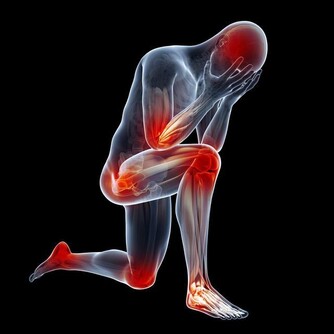

1、嗜睡貪睡 2、大便溏瀉 3、舌苔厚膩 4、腹部肥胖 5、怠惰嗜卧 6、下肢沉重 7、脘腹脹滿 8、精力下降 9、情緒抑鬱10、痰多而粘。